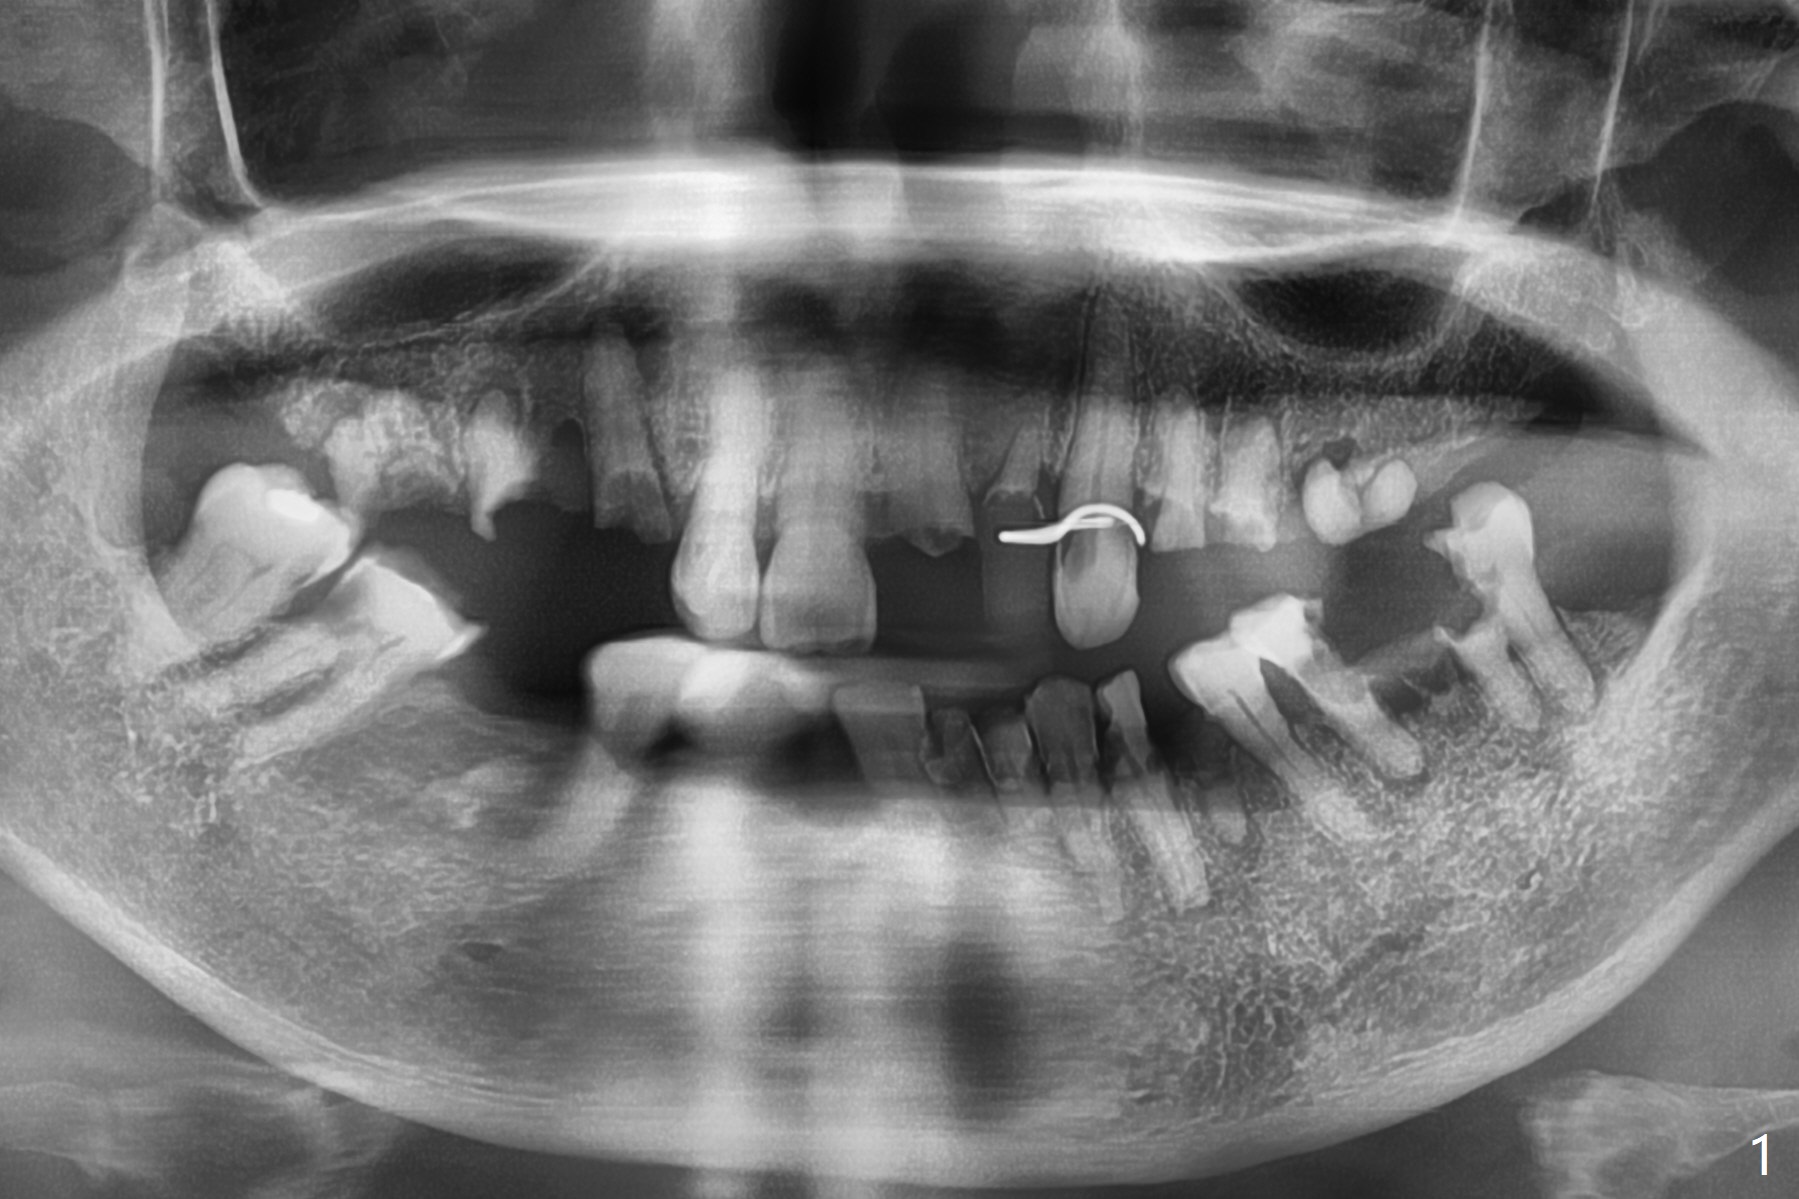

A 86-year-old woman with diabetes (under control with Insulin) and poor dentition (Fig.1) presented to clinic with an abscess apical to the tooth #8 (nonvital, Fig.2). CBCT (Fig.3) or PA (Fig.4) does not show radiolucency at #7 or 8. The incised abscess with purulent drained is superficial to the apparently intact periosteum (Fig.5 *). The patient is reluctant to have #7 and 8 extracted, since they are the only remaining functional dentition. The infection recurs 1.5 months later (Fig.6 * (^: previous incision)). With the periosteum elevated, fenetration over the apex of the tooth #7 (vital in pulpal test) is only seemingly significant finding (Fig.7). The abscess (Fig.8 A) is shown superficial to the periosteum (*). The infection is expected to relapse. What should be done otherwise? Full mouth extraction has been discussed.